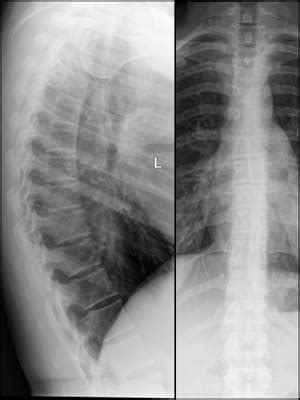

So, how do thoracic spurs actually show up on an X-ray ? Let’s get into the nitty-gritty. An X-ray is essentially a type of imaging test that uses electromagnetic radiation to create pictures of the inside of your body, specifically your bones. When it comes to thoracic spurs , the X-ray is able to clearly visualize these bony growths. In the X-ray images, thoracic spurs typically appear as small, pointy or irregular projections that stick out from the edges of the vertebrae. They can vary in size and shape. You might see them as tiny, subtle bumps, or they could be larger and more pronounced. The radiologist or doctor looks for these abnormalities along the vertebral bodies and the facet joints, which are the areas where the vertebrae connect. Depending on the position and angle of the X-ray , the spurs might appear more or less prominent. Sometimes, they can be quite obvious; other times, they require a trained eye to spot them. The specific appearance of the spurs on the X-ray can provide clues about the underlying cause and severity of the condition. For example, the location of the spurs can help pinpoint which part of the spine is most affected. Also, the size and number of spurs can provide an indication of the extent of the spinal changes. The X-ray also helps doctors rule out other possible conditions that may be causing similar symptoms. The X-ray doesn’t provide the complete picture. Further tests might be needed to determine if the spurs are causing any symptoms or if there’s any damage to the surrounding tissues.

When reviewing an X-ray , healthcare professionals will look at several key features. Firstly, they examine the alignment of the vertebrae, looking for any signs of curvature or instability. Next, they carefully assess the bone density, searching for signs of wear and tear, and the presence of any other abnormalities. They will note the size, shape, and location of any thoracic spurs . The presence of other conditions is assessed as well. These are vital for determining the overall health of the spine. The X-ray provides essential information, but further evaluation might be required for a detailed understanding of the patient’s condition. Remember, interpreting an X-ray is a job for trained professionals. They can make accurate diagnoses and create effective treatment plans. Let’s delve deeper into how these spurs are diagnosed and what treatments might be in store.